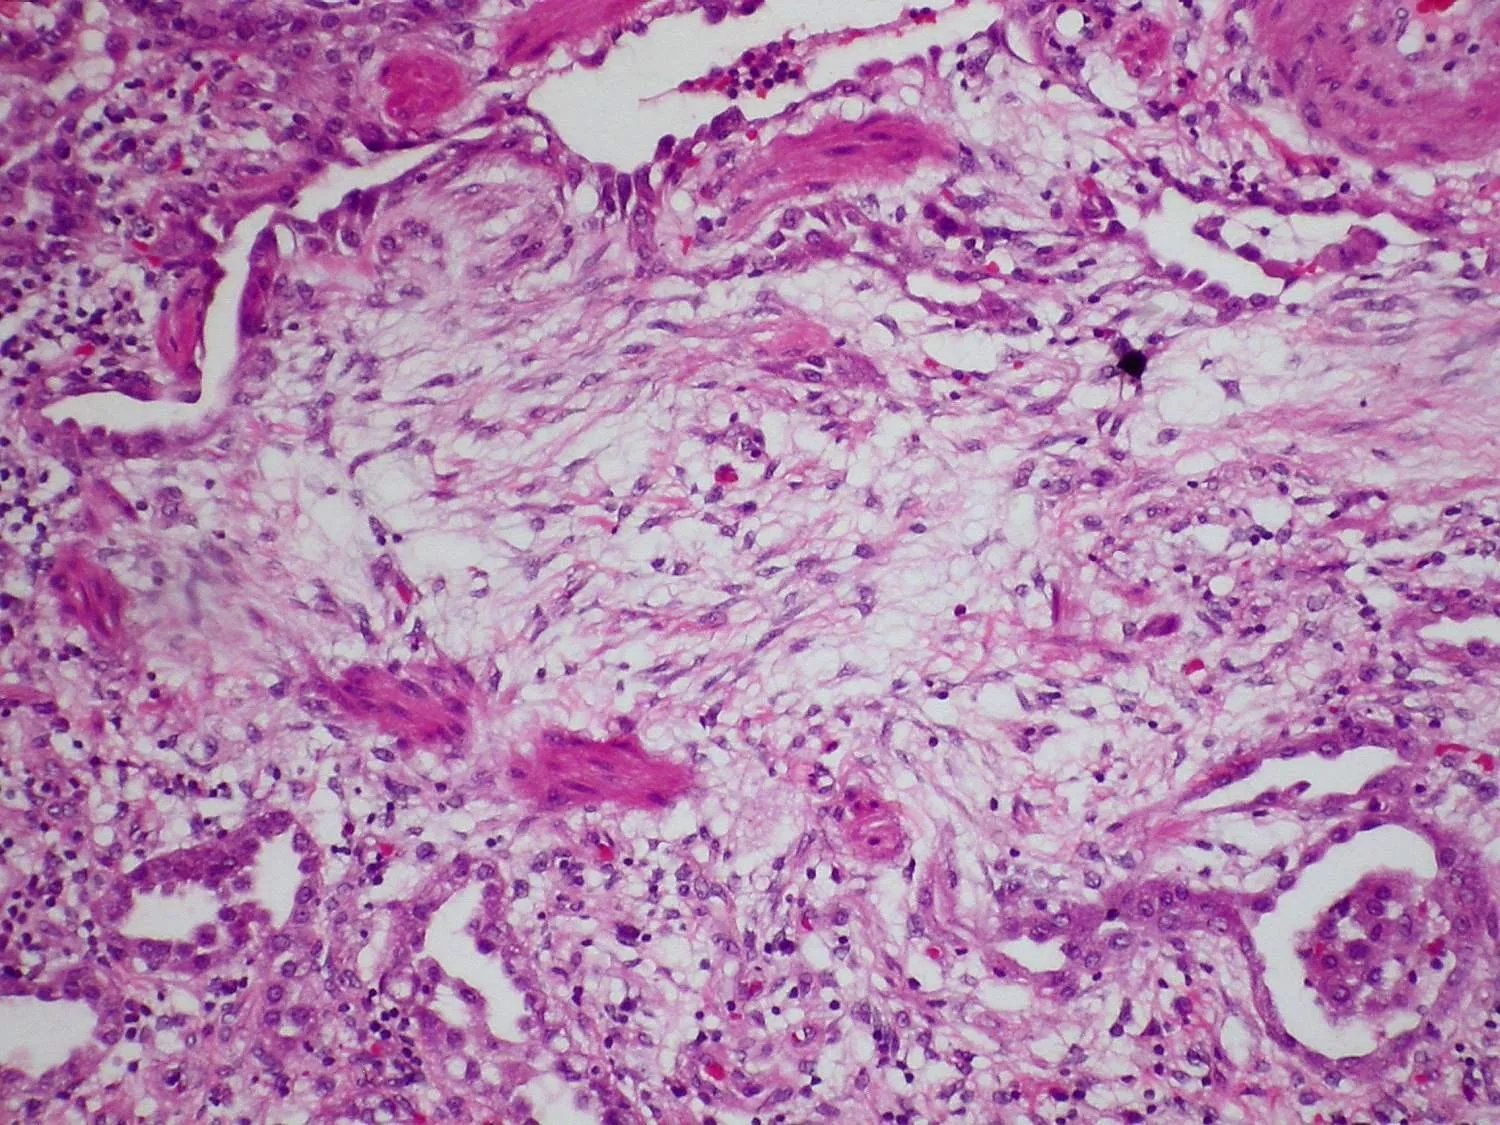

Az elváltozás tüdőszöveti mikroszkópos képe

Fibrotikus elváltozás a tüdőben, fibroblasztok tömege (forrás: Yale Rosen, liszensz: CC BY-SA 2.0, Wikimedia Commons)

Ha a sclerosis a tüdőt is érinti és hegesedést okoz, akkor szisztémás sclerosissal összefüggő intersticiális (kötőszöveti) tüdőbetegségről beszélünk (SSC-ILD). Ebben az esetben a tüdő léghólyagjai hegesek és gyulladtak lesznek, amely rontja a tüdő funkcióját, a tüdő merevvé válik, így veszít teljesítményéből. A hegek megjelenése miatt a scleroderma ezen szövődményét tüdőfibrózisnak is szokás nevezni.